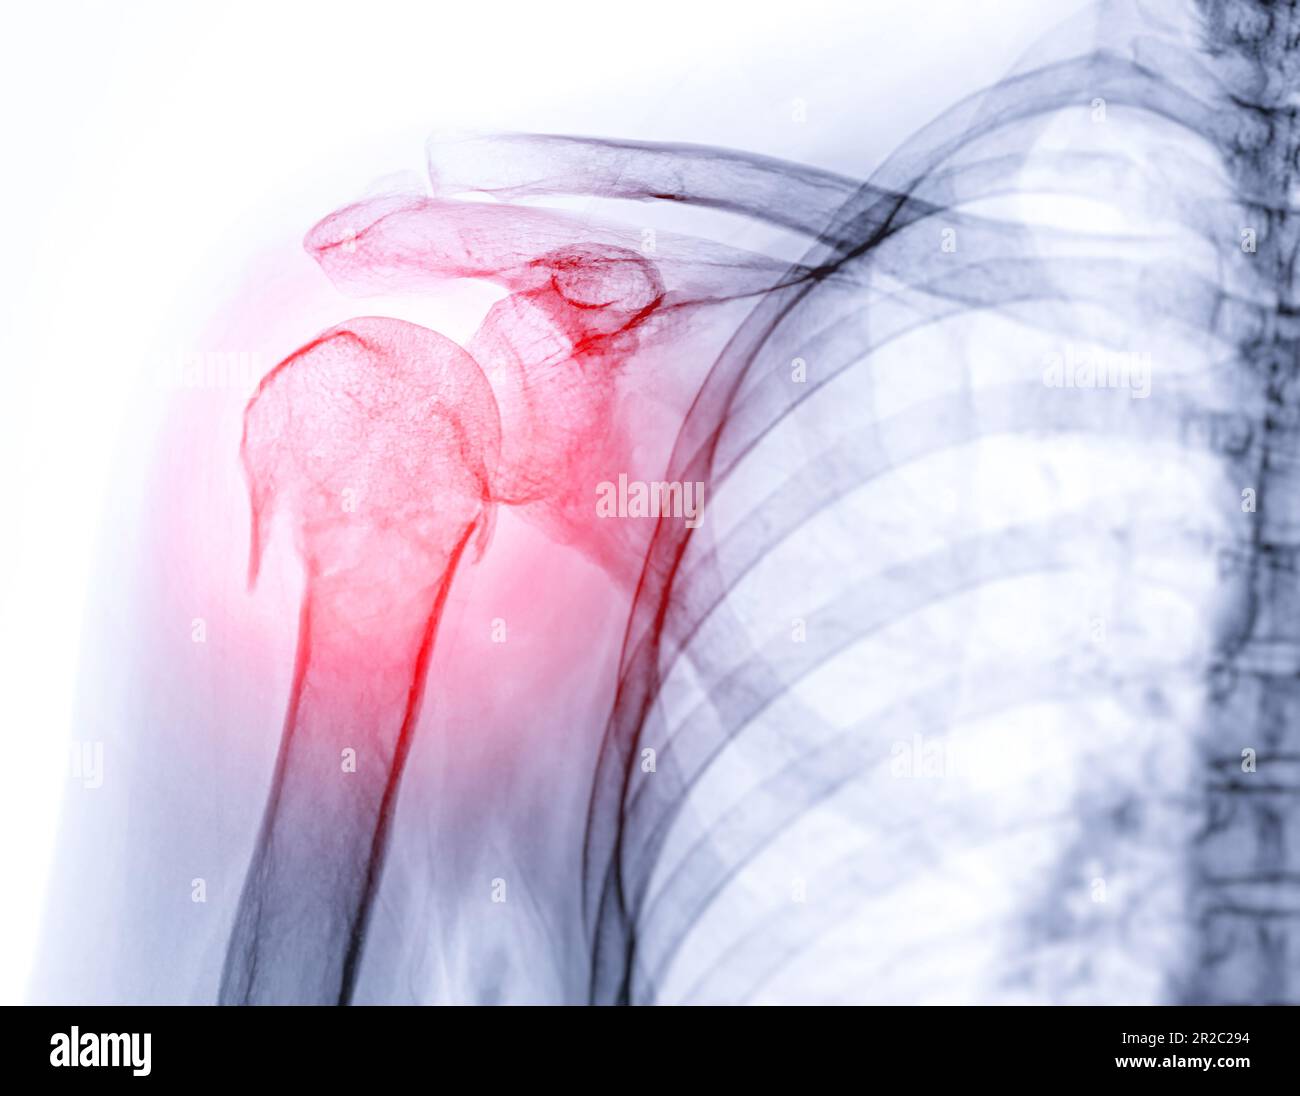

Shoulder Joint Fracture X Ray  Sometimes, additional imaging techniques, such as a. The humeral head should be on the glenoid in any other.   diagnosis is made with orthogonal radiographs of the shoulder. Sometimes, additional imaging techniques, such as a.   in this review, we will discuss the mechanisms of injury, key imaging findings, therapeutic options and. Magnetic resonance imaging (mri) :. Treatment with sling immobilization is indicated for minimally displaced. Front and side pictures show the swelling and bruising down the arm. Articular surfaces should be parallel.   the neer system divides the proximal humerus into four parts and considers not the fracture line, but the displacement as being significant in terms. A patient with a proximal humerus fracture.

Xray Shoulder Joint Shoulder Transaxillary View for Diagnosis Fracture of Shoulder Joint Stock Shoulder Joint Fracture X Ray  The humeral head should be on the glenoid in any other. A patient with a proximal humerus fracture.   diagnosis is made with orthogonal radiographs of the shoulder. Magnetic resonance imaging (mri) :.   in this review, we will discuss the mechanisms of injury, key imaging findings, therapeutic options and. Articular surfaces should be parallel. Sometimes, additional imaging techniques, such. Shoulder Joint Fracture X Ray.